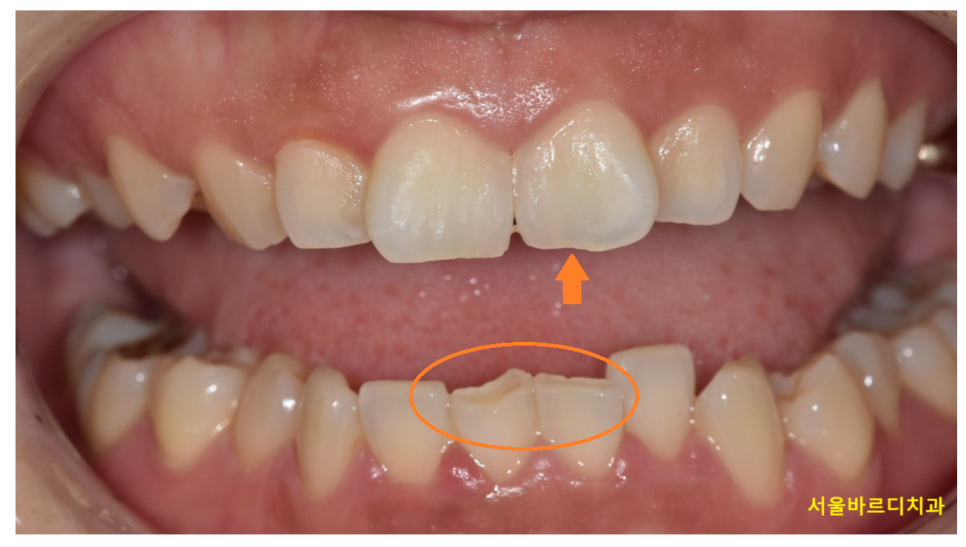

보통 다음과 같은 모습이 관찰됩니다

이를 앙 물었을 때 아래 치아가 거의 보이지 않거나

윗니가 아랫니를 과도하게 덮는 모습이죠.

어떤 경우에는 아랫니가 윗 치아와 닿아

갈려 나가는 마모된 모습을 관찰할 수 있습니다.